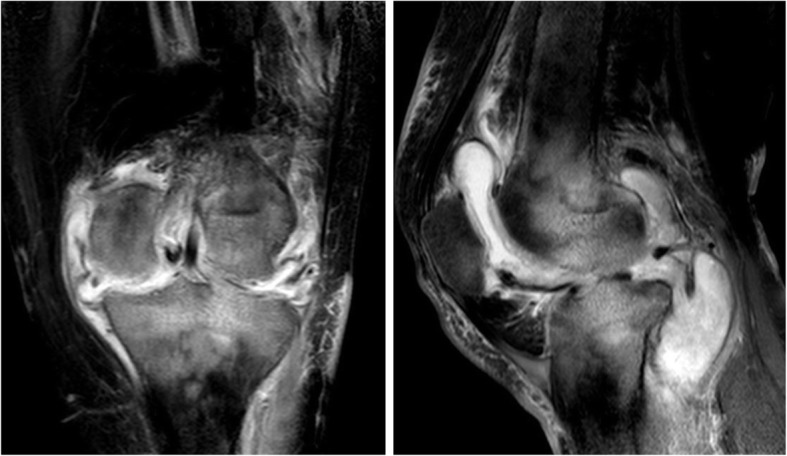

Fig. 3.

MRI (anteroposterior and lateral): synovial hypertrophy, unclear boundary of surrounding soft tissue, clear scope of cold abscess, severe joint destruction, obscure subcartilaginous bone plates, and central and peripheral erosions